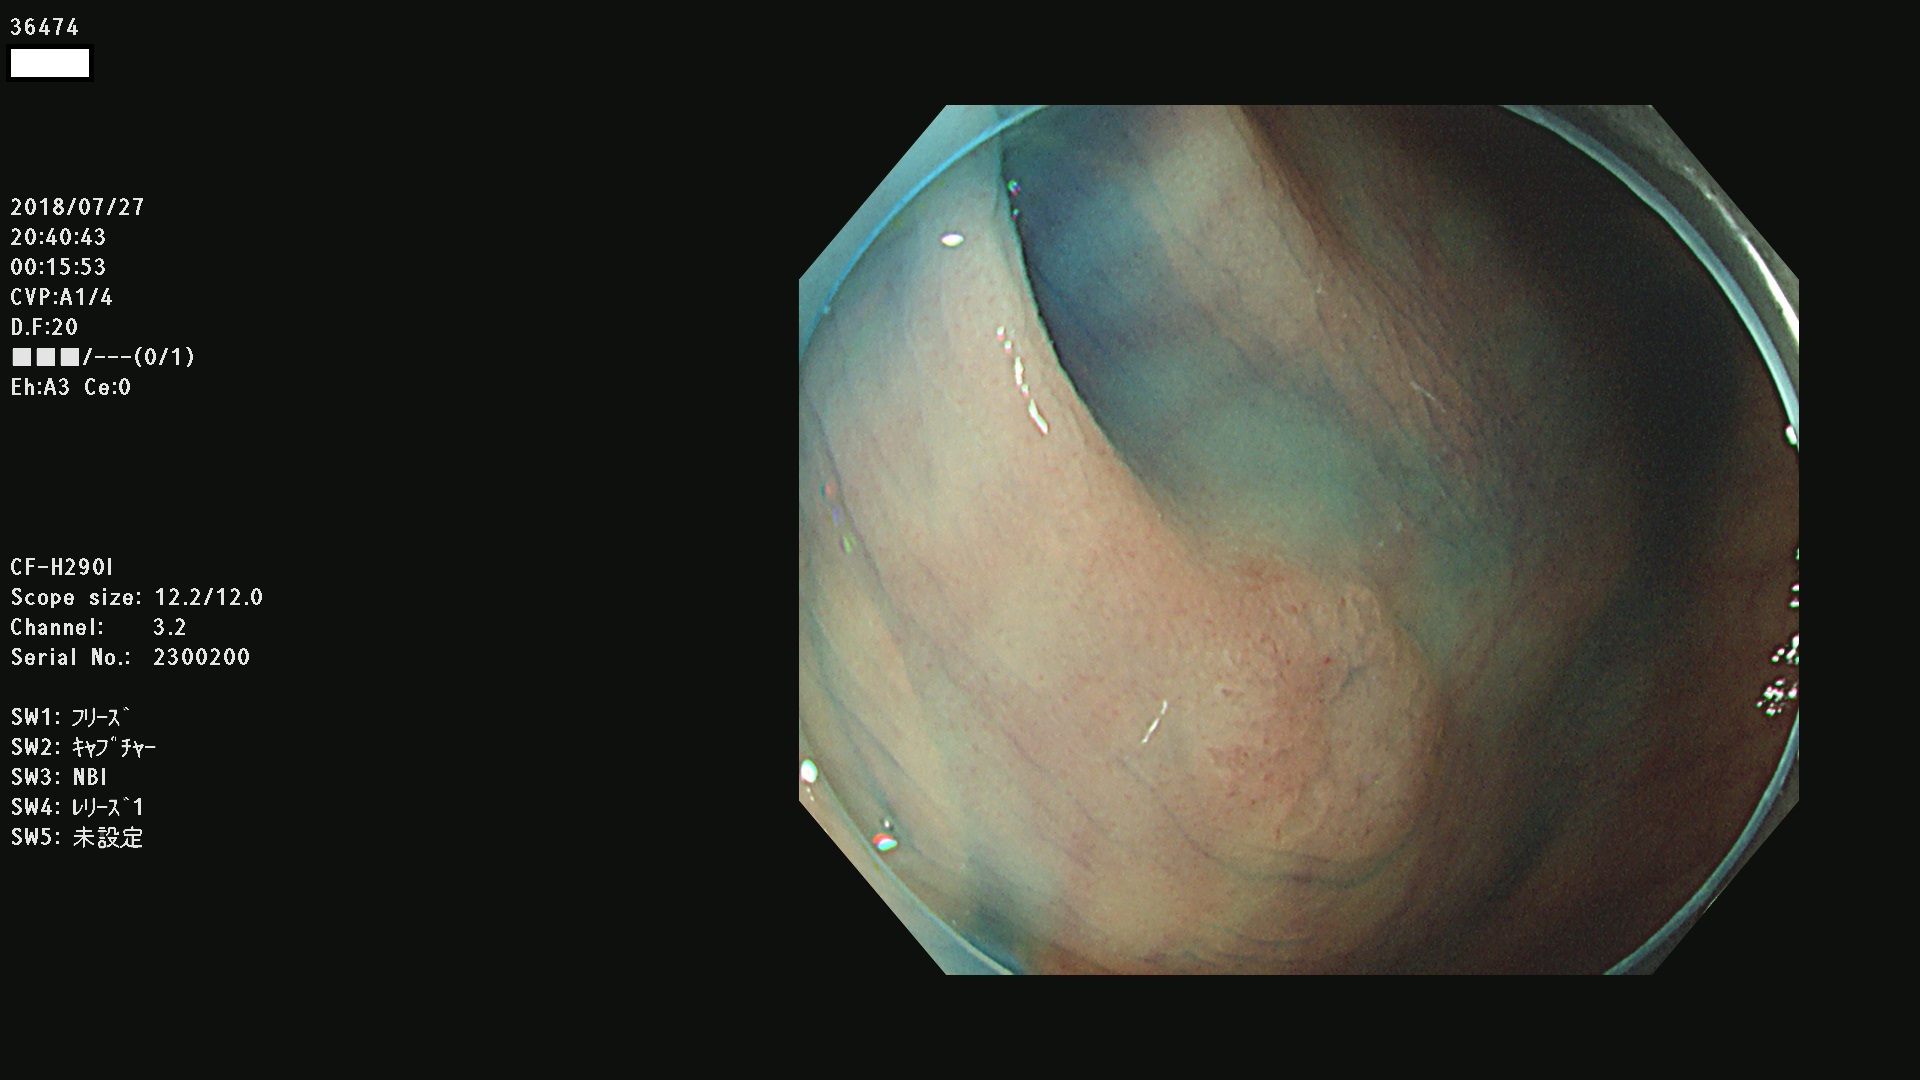

36400(SSAPのみ) 36402 36403 36404 36405 36406 36407 36408(SSAPのみ) 36412 36413 36414 36415 36416 36417 36418 36420 36422 36423 36424 36425 36426 36428 36429 36430 36431 36434 36435 36436 36437 36438 36440 36443 36447 36448 36449 36450 36452 36454 36458 36459 36460 36462(SSAPのみ) 36463 36464 36465 36466 36470 36471 36472 36473 36474 36475 36476 36478 36480 36481 36482 36484 36487 36488 36489 36490 36492 36494 36495 36496 36497 36498